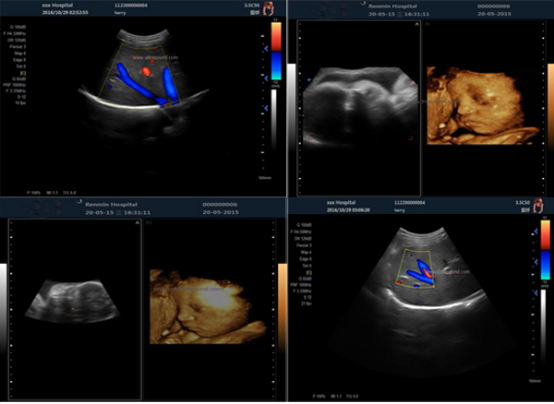

4D image technology hot sell portable pregnancy ultrasound

clear image

4d Image Technology Color Doppler Ultrasound Scanner For Pregnancy Ultrasound Images |